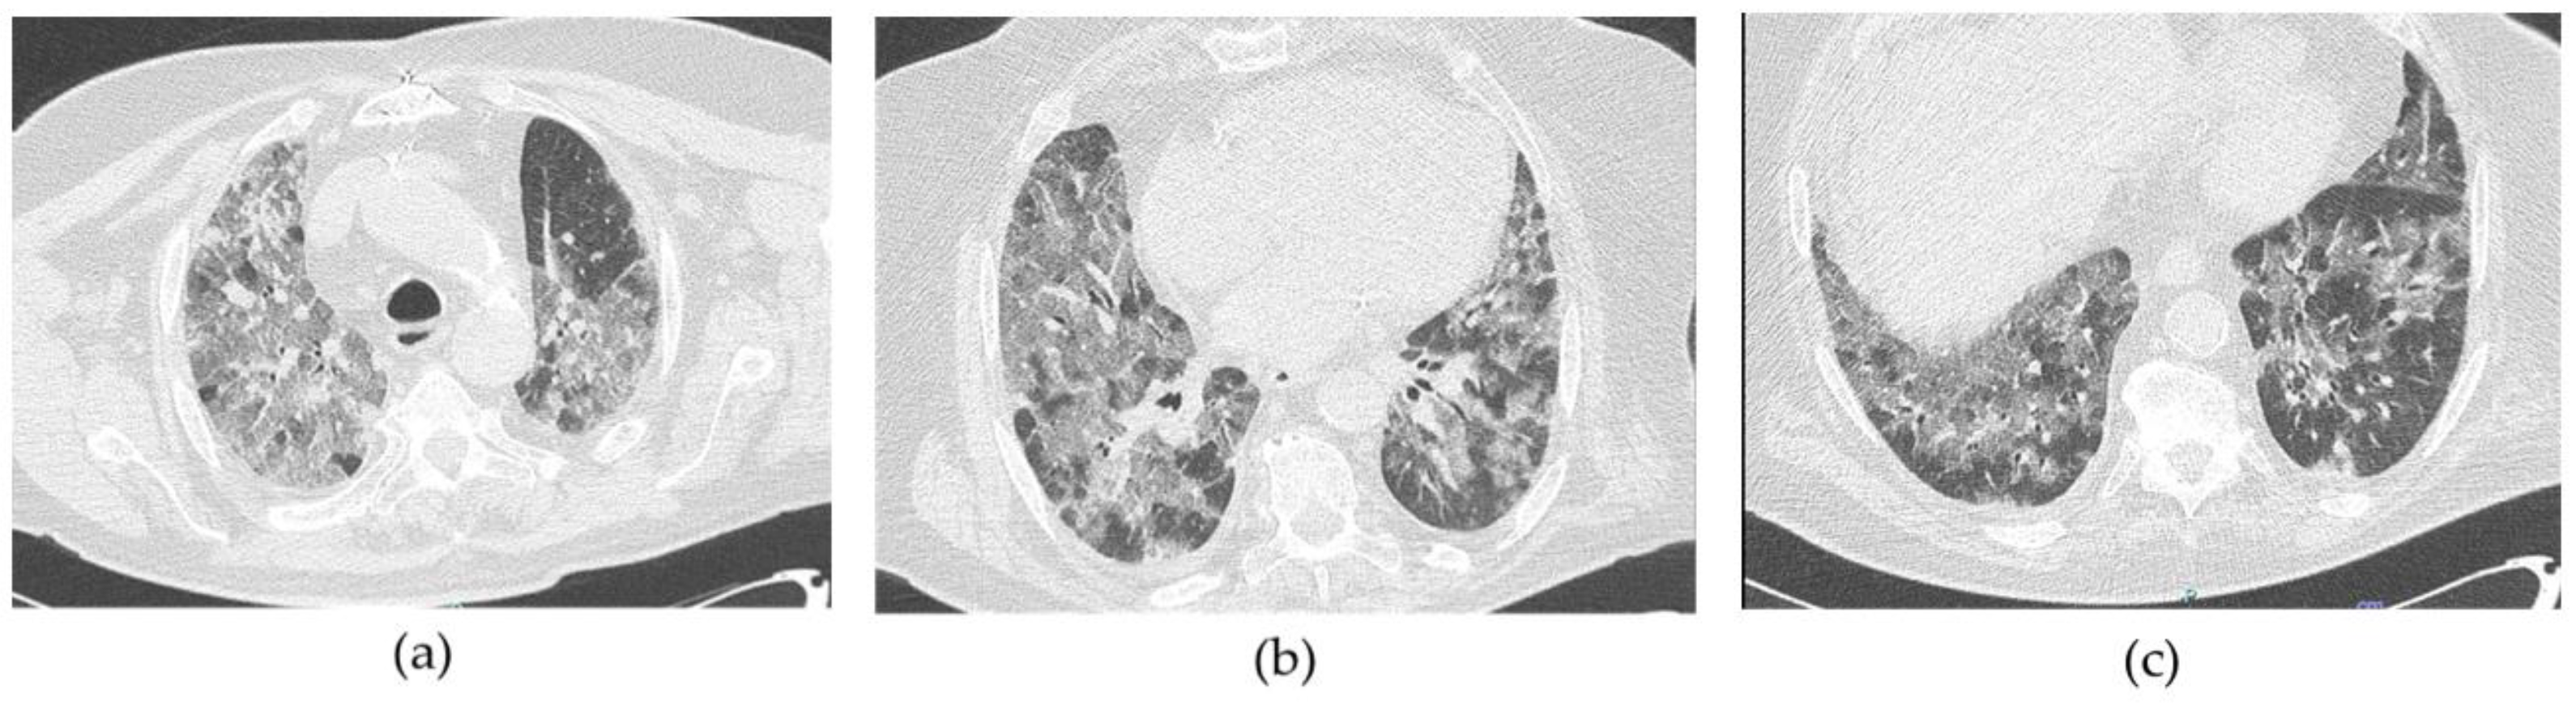

4.3. CT Scan Description